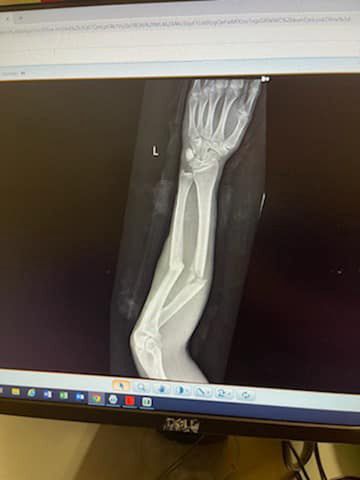

Równie koszmarnie co zdjęcia opublikowane chwilę po wypadku wygląda kopia RTG wykonanego w szpitalu. Wyraźnie widać na nim zniszczenia jakie wyrządził upadek z wysokiego konia. Teraz dżokej będzie musiał skupić się na rehabilitacji, aby odzyskać jakąkolwiek sprawność w kontuzjowanej ręce.

koszmat rtg koby jennings

RTG Koby'ego Jenningsa © Twitter.com